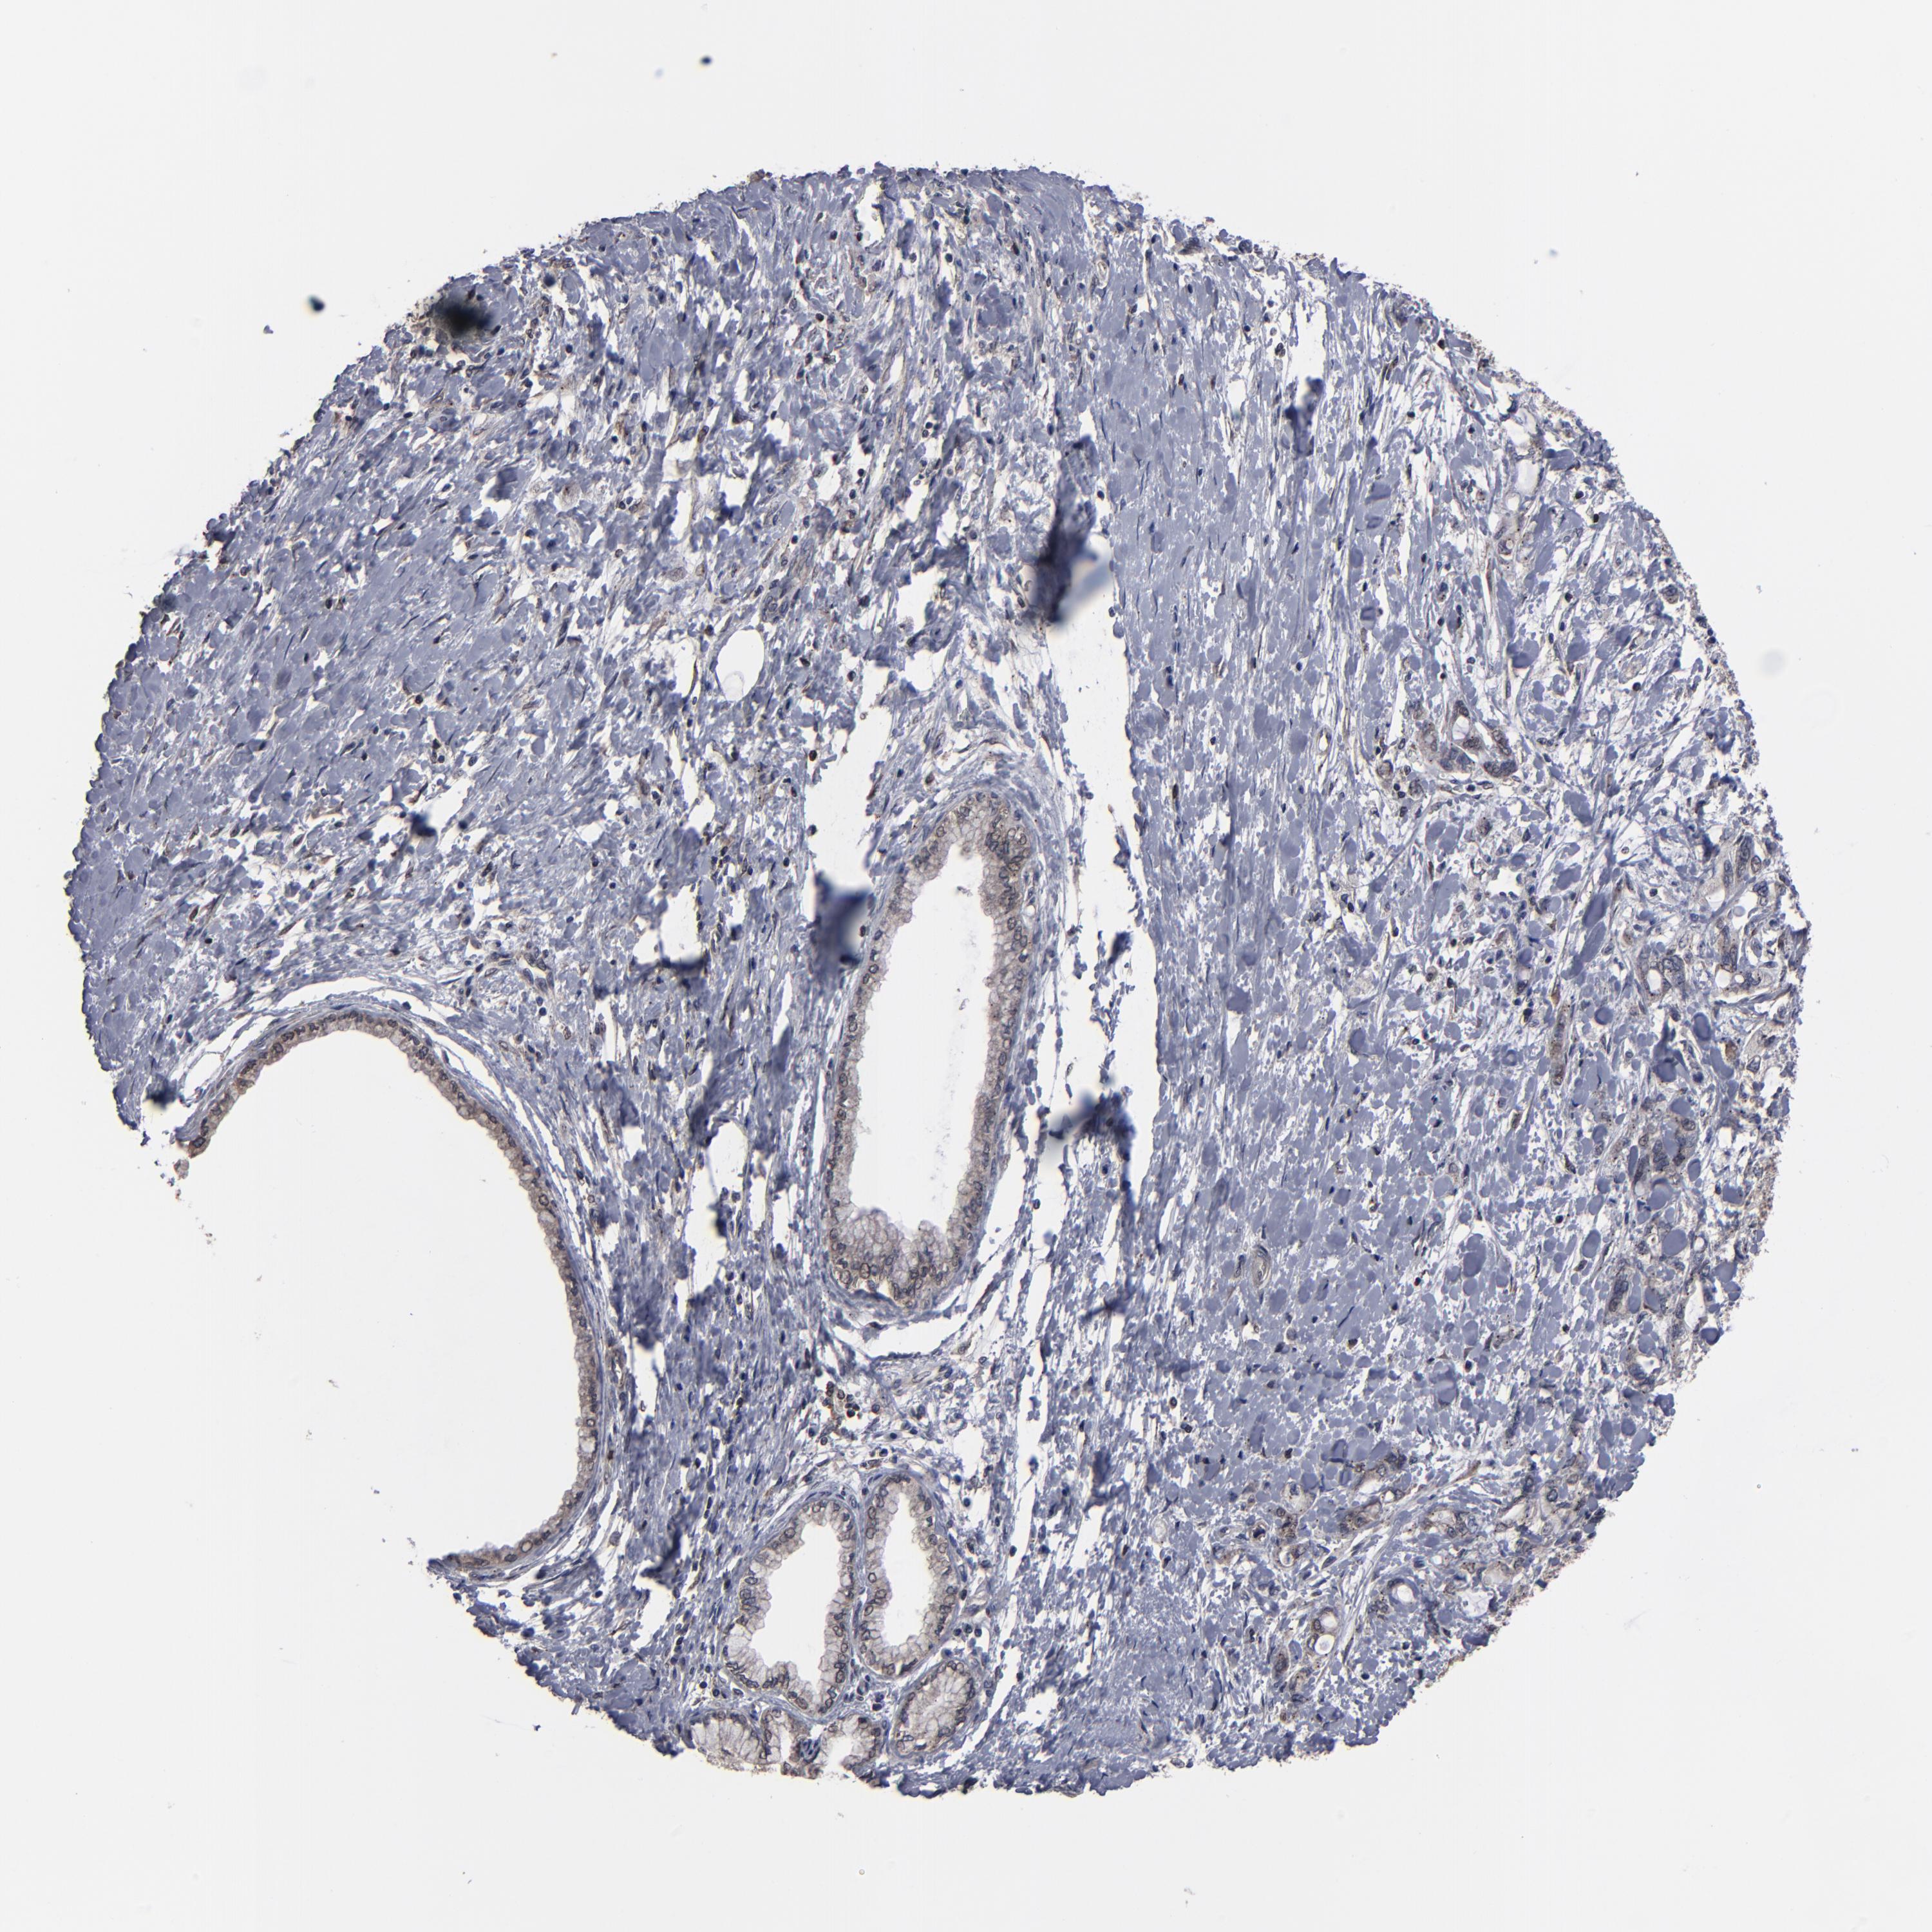

PANCREATIC CANCER - Protein expressioni

A mouse-over function shows sample information and annotation data. Click on an image to view it in a full screen mode. Samples can be filtered based on level of antibody staining by selecting one or several of the following categories: high, medium, low and not detected. The assay and annotation is described here.

Note that samples used for immunohistochemistry by the Human Protein Atlas do not correspond to samples in the TCGA dataset.

Antibody stainingi

Antibody staining in the annotated cell types in the current human tissue is reported as not detected, low, medium, or high, based on conventional immunohistochemistry profiling in selected tissues. This score is based on the combination of the staining intensity and fraction of stained cells.

Each image is clickable and will lead to virtual microscopy that enables deeper exploration of all samples and also displays staining intensity scores, fraction scores and subcellular localization as well as patient and tissue information for each sample.

Antibody HPA002109

Staining

High

Medium

Low

Not detected

Intensity

Strong

Moderate

Weak

Negative

Quantity

>75%

75%-25%

<25%

None

Location

Nuclear

Cytoplasmic/membranous

Cytoplasmic/membranous,nuclear

Adenocarcinoma, NOS

Adenocarcinoma, metastatic, NOS